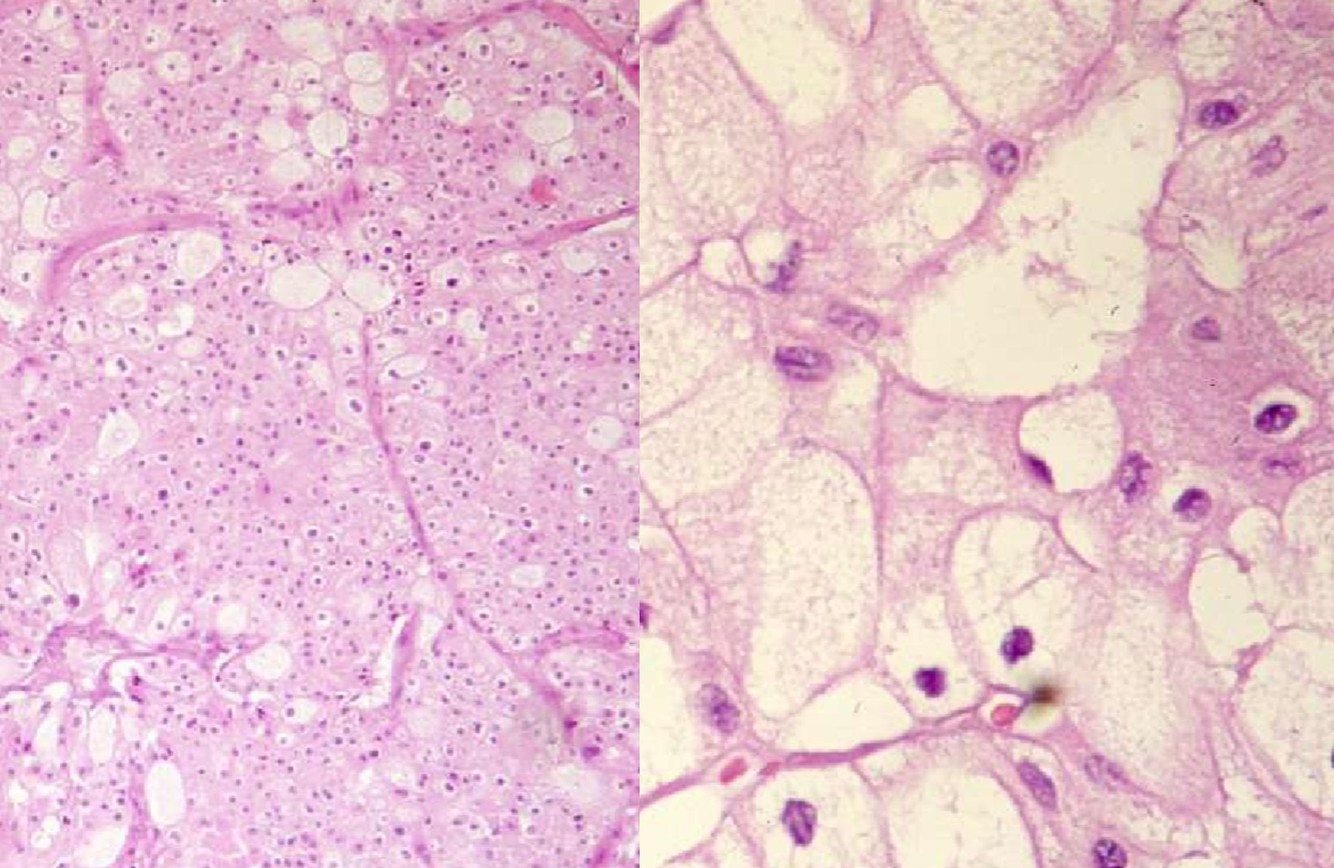

XANTHOGRANULOMATOUS PYELONEPHRITIS

- Often associated with large staghorn calculi of renal pelvis

- Many of these patients may have UTI, secondary to E. coli or Proteus

- May presents as a mass-like lesion